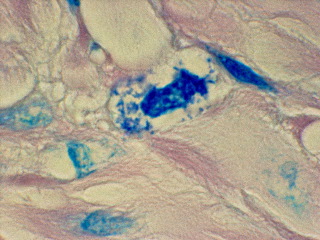

- Fig 1

-

- Like bacteria observed in other forms of cancer, prostate

cancer bacteria are primarily observed in the connective tissue stroma

in tightly-packed clusters of round "coccoid" forms seemingly

embedded in a matrix. These microbes can be seen, although with difficulty,

by using the "high power" lens of the microscope, which magnifies

400 times (Figures 1 and 2). Using oil and the oil-immersion lens, which

allows magnification up to 1000 times, the organisms are seen more clearly.

The forms are primarily seen packed together in tight units in the connective

tissue stroma (Figure 3). Sometimes a cell nucleus is clearly visible in

the cluster (Figure 4). Rarely, one can see intracellular forms which suggest

short rod-shaped bacterial forms, rather than the common round coccoid

forms (Figure 5). Extracellular forms that escape from the tight bacterial

clusters can be seen scattered in the connective tissue (Figure 6). Occasionally

larger coccoid forms are seen that are three and four-times larger than

the tiniest round forms. The largest round spore-like forms seen in Figure

6 are apparently what Russell observed as his "parasite of cancer."

- Figure 1: Tissue section from prostate adenocarcinoma

showing, in center, a cluster of tightly-packed intracellular blue-stained

coccoid forms. Fite (acid-fast) stain, magnification x 400 ("high

power").

- Figure 2: Prostate cancer. In center, additional focus

of intracellular blue-stained coccoid forms. Fite stain, magnification

x 400 ("high power").